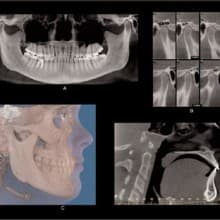

Cone Beam CT: A Breakthrough Imaging Technology for Dentistry

ABSTRACT: Accurate images of the craniofacial region are critical for the development of a diagnosis and treatment plan. The Cone Beam CT (CBCT) Scanner represents a significant advance in imaging capabilities for all disciplines of dentistry. This new-generation scanner uses computed tomography technology to provide a complete three-dimensional view of the maxilla, mandible, teeth, and supporting structures with relatively high resolution and low radiation exposure to the patient. This article discusses some of the technical aspects of CBCT and its possible dental usages. INTRODUCTION: Images of the craniofacial region comprise an important component of the dental patient record. Ideally, the imaging process begins with the development of an imaging goal. The imaging

Exploring Cone Beam 3–D Dental Imaging

2-D imaging (standard film and digital X-rays) has long been the standard for dental scans-despite the somewhat costly price and high radiation dosages. Now 3-D imaging technology is set to address these issues. Cone Beam technology obtains crucial information at much higher resolution using lower radiation, and is cost-effective for practitioners and patients. Indeed, such important benefits will certainly give traditional 2-D X-ray imaging a run for its money. THE INTRODUCTION OF CONE BEAM TECHNOLOGY Here's where 3-D imaging is invaluable. It lets dentists see patients' anatomies in all dimensions by creating a 360° analysis. These images give dental professionals a complete makeup of the human jaw, face, and